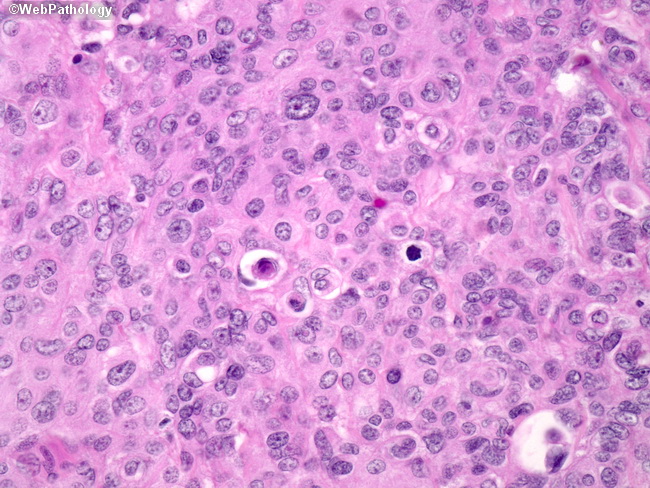

Микрофотографии гистологии глиобластомы головного мозга